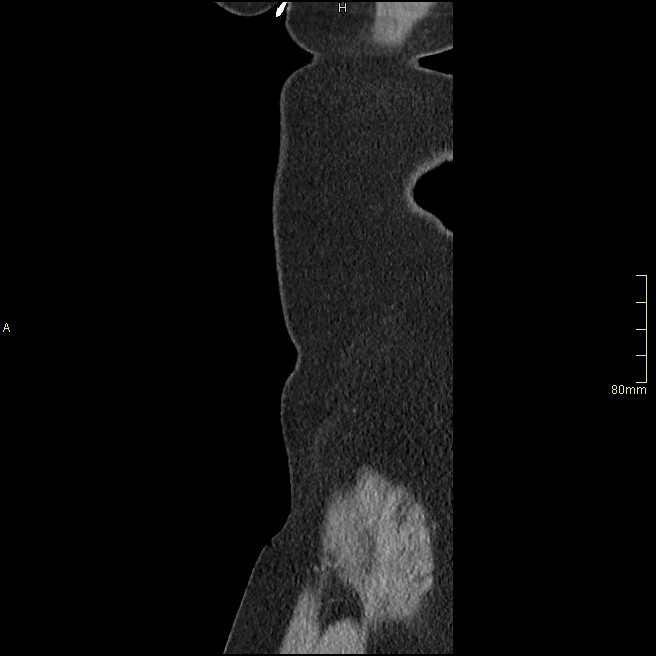

For patients over the age of 40, a non contrast KUB, and seperate nephrogenic and excretory (delayed) phases will be performed. For all patients under the age of 40, a non contrast KUB and a COMBINED dual nephrogenic/excretory phase will be performed. Image examples of this can be seen below.

Over 40 Years of Age

CT Urogram- Nephrogenic Phase (Axial)

CT Urogram- Excretory Phase (Axial)

CT Urogram- Nephrogenic Phase (Coronal)

CT Urogram- Excretory Phase (Coronal)

CT Urogram- Nephrogenic Phase (Sagittal)

CT Urogram- Excretory Phase (Sagittal)